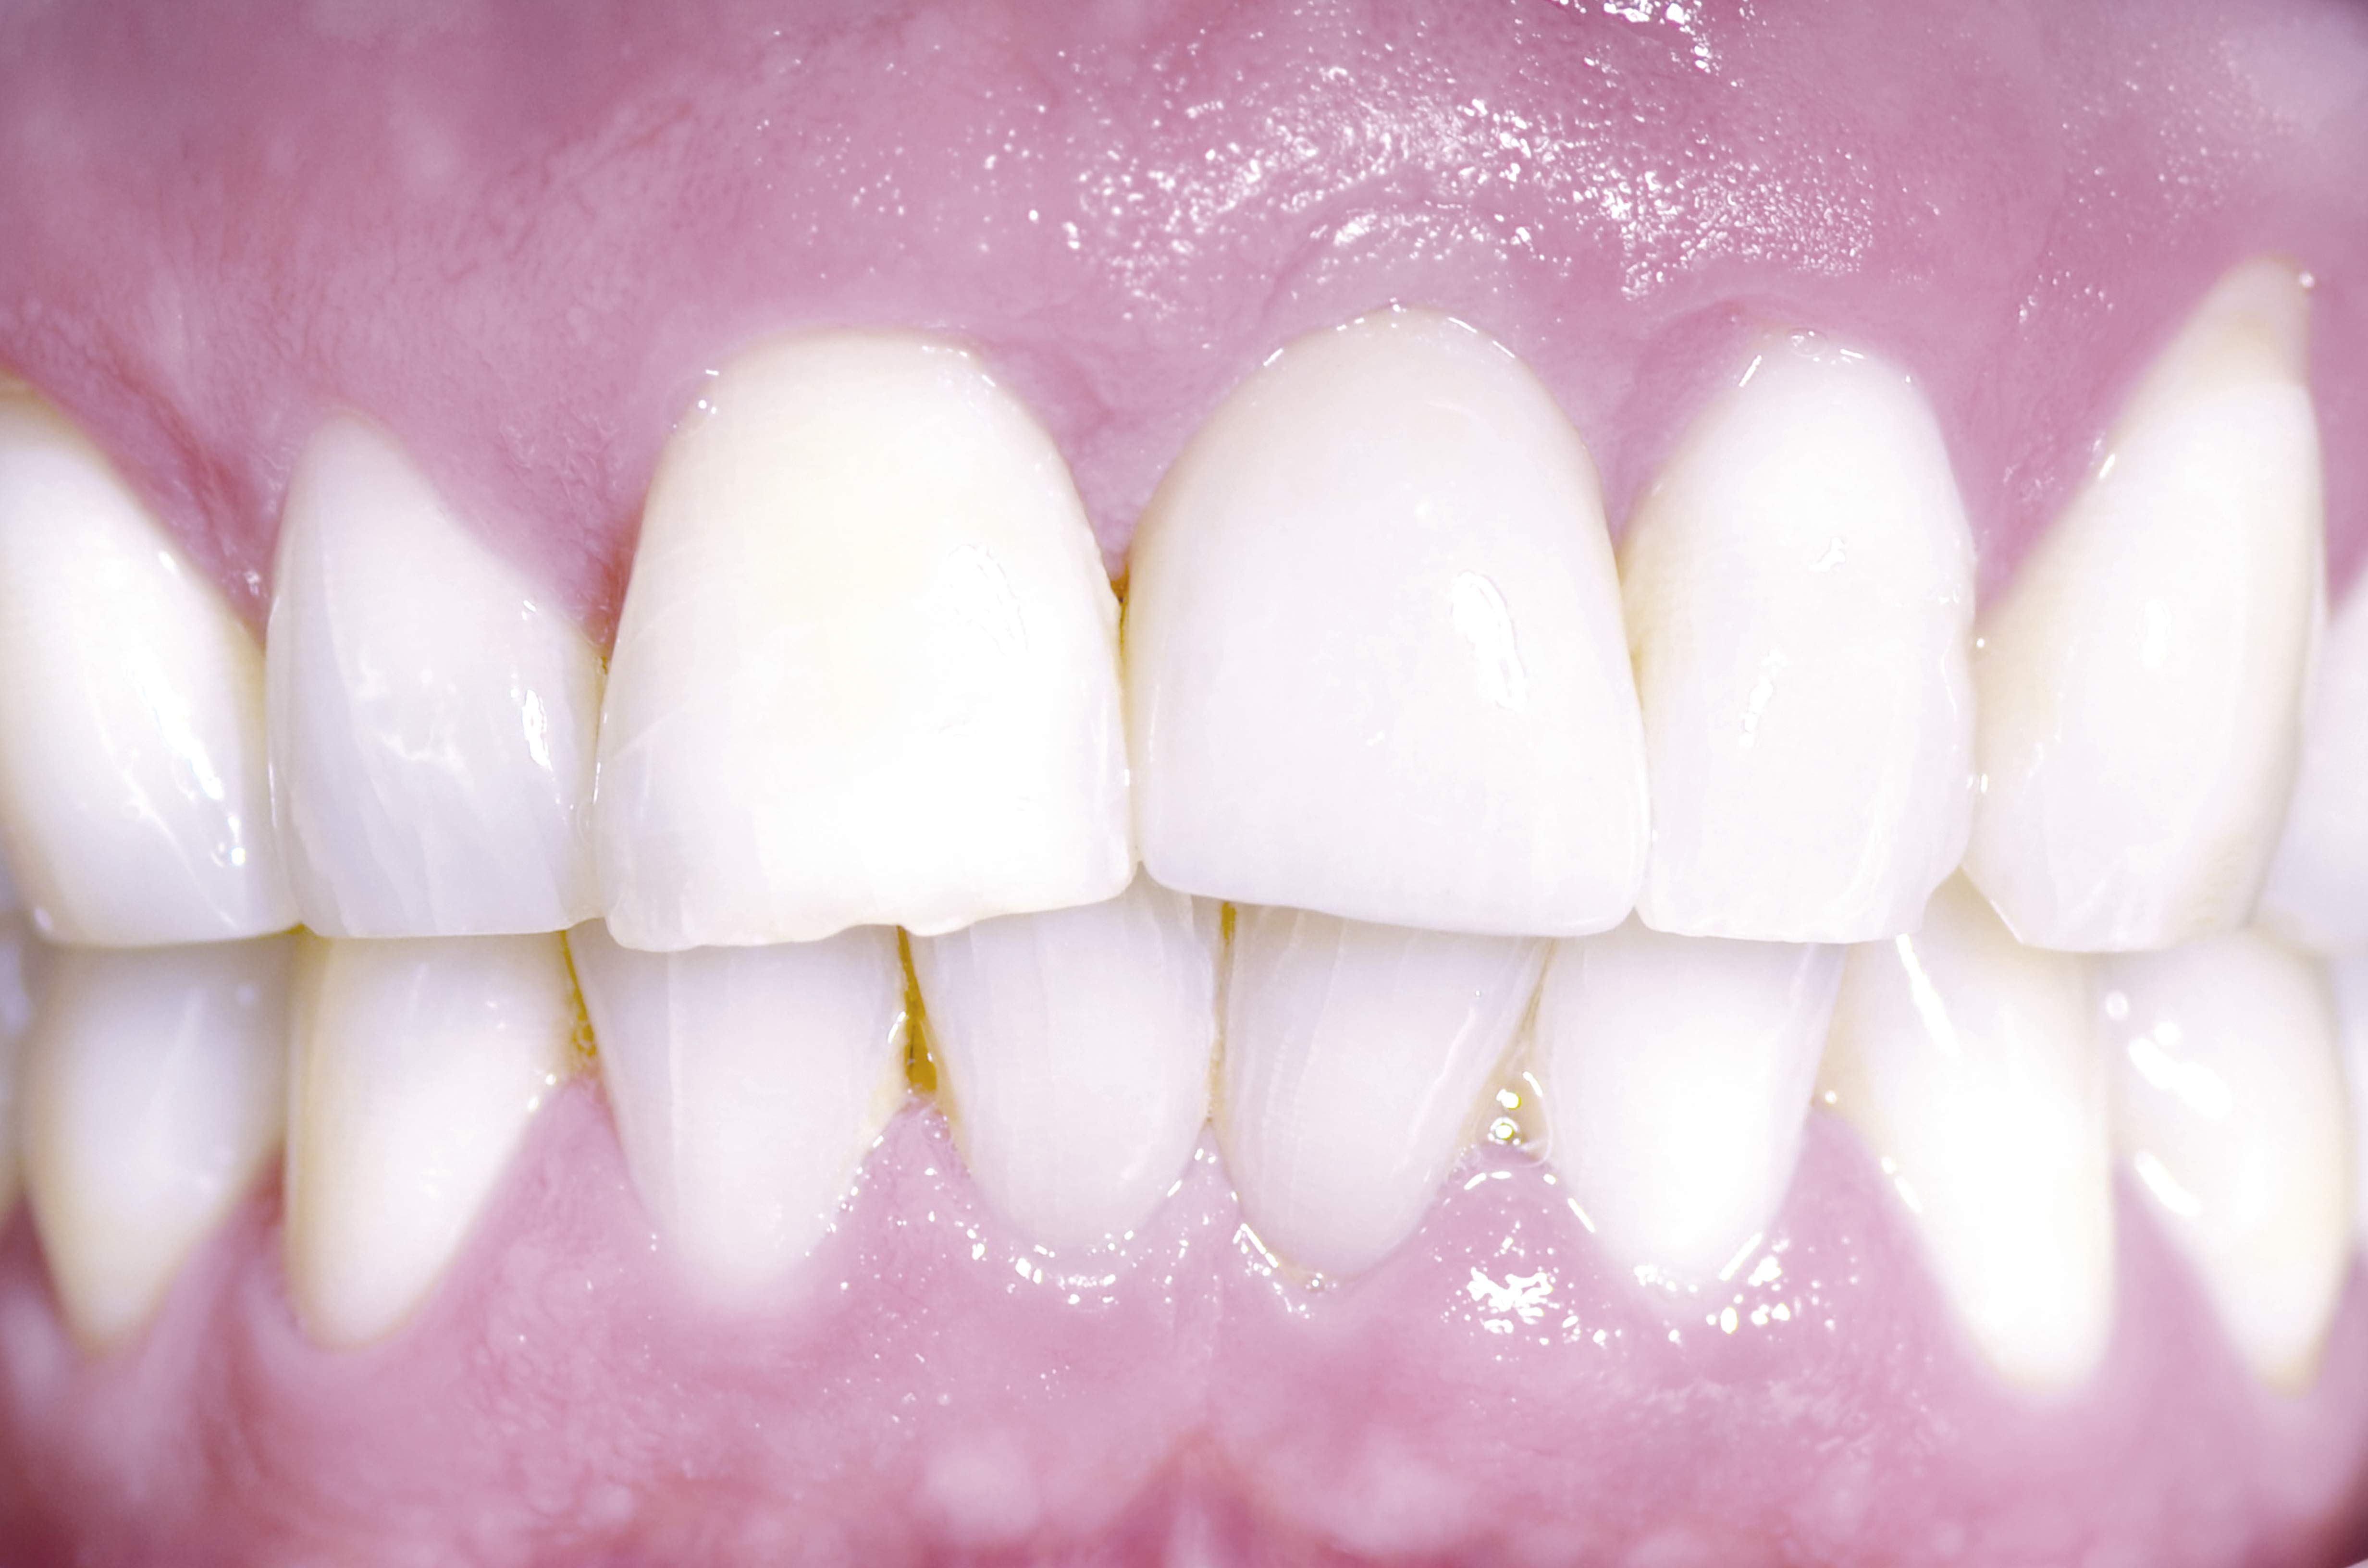

02/18 - Clinical situation after tooth extraction